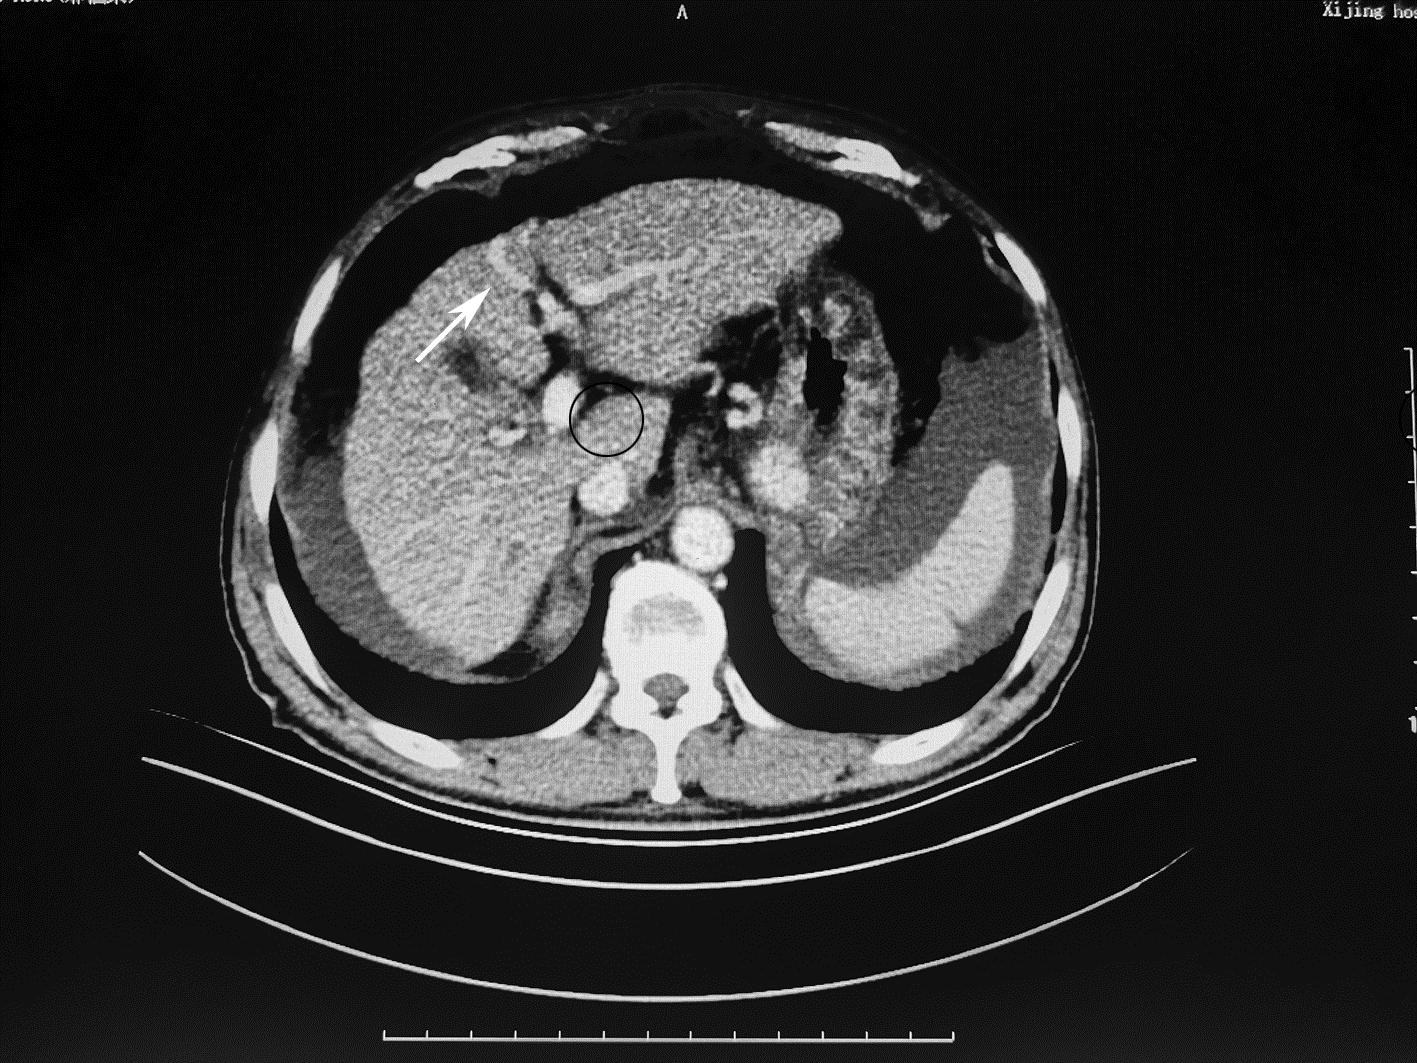

局部栓塞联合靶向免疫综合治疗肝肉瘤样癌1例报告

摘要(1328) HTML (453) PDF (3487KB)(83)

摘要: